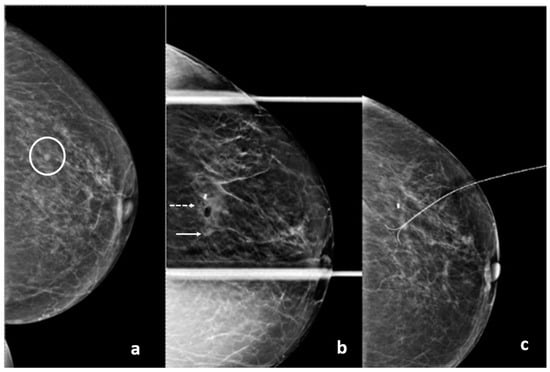

Figure 4. The lesion detected on the planning tomosynthesis image (circle) is masked by the artifact on the post-fire image.

Figure 15. Left: prebiopsy image showing a suspicious distortion (circle). Right: The biopsy cavity and clip marker are both centered at the lesion.

Figure 16. (a) Pre-biopsy mammogram revealing a mass in the inner quadrant of the left breast. (b) Post-biopsy mammograms revealing a cavity centered at the lesion (circle) but lateral displacement of the clip marker (arrow).

Figure 17. (a) A 65-year-old patient with a screen-detected left breast mass (circle). (b) Post-procedure mammograms after DBT-guided biopsy show the biopsy cavity and clip marker (dashed arrow) to be laterally located with respect to the mass (arrow). Pathology shows atypical ductal hyperplasia. Because of concern about proper sampling and radiological-pathological discordance, a surgical excision after wire localization was performed (c). Final pathology reveals a grade 1 invasive ductal carcinoma.